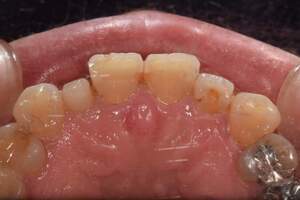

歯石除去

治療前

治療後

| 年齢 | 40歳・男性 |

| 主訴 | 歯石をとりたい |

| 治療内容 | 歯石除去 |

| 治療期間 | 30分 |

| 費用 | 約2,000円 |

| リスク・副作用 | ・歯ぐきの炎症が強いと歯石を取る際に出血することがあります。 ・処置後に歯がしみることがあります。 ・歯と歯の間に隙間ができるので、息が漏れ発音しにくいと感じることがあります。 ・歯ぐきの炎症が軽減すると歯ぐきが引き締まり、歯が長く見えることがあります。 |